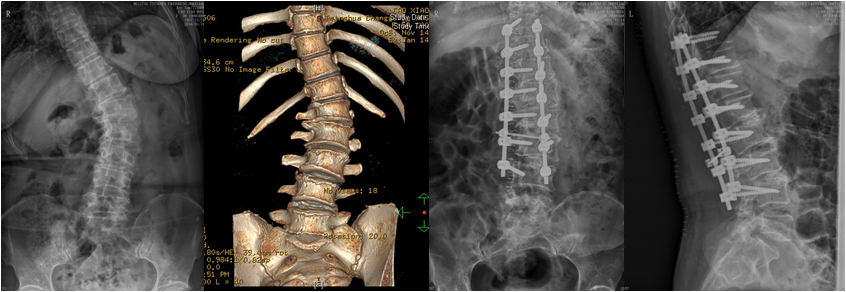

腰椎退行性侧后凸伴椎管狭窄;减压截骨矫形固定融合

在肖嵩华主任的带领下,医院春节后先后收治4例较为复杂的脊柱侧弯患者。一例儿童先天性脊柱侧弯,半椎体合并分隔不全;一例腰椎退变性侧弯伴间盘源性腰痛;一例腰椎后凸畸形,矢状面失平衡,无法直腰行走;一例胸腰椎退变性侧后凸伴椎管狭窄,下肢疼痛麻木严重。

经完善三维影像学检查,脊柱专业组查房讨论,分别针对4例患者,制订个体化精准减压矫形方案,由肖嵩华教授主刀,宋飞主治医师和脊柱组医师配合,在连续的4个手术日,分别完成胸6半椎体切除胸廓成形矫形固定,腰椎后凸截骨矫形固定融合,退变性侧弯减压矫形固定融合,侧后凸减压截骨矫形融合固定,4台高难度手术均告成功。12岁的男孩是第一个接受手术的患者,男孩父母的心理压力非常大,待医师走出手术室,告知手术成功时,一直坚强的母亲眼泪瞬间流了下来,“这场手术把孩子的命运带回了正常的轨道。”

患者脊柱畸形得到纠正,伴随的椎管狭窄压迫神经等症状也得到彻底根治。困扰患者多年的躯干外形异常和神经功能障碍一去不复返。术后2-3天,4位患者均可下地,“腰杆子直起来了”;“大腿不疼不麻,能正常走路了”;“身高增加了”,脊柱畸形患者术后效果良好,可谓:新年开了个好头。